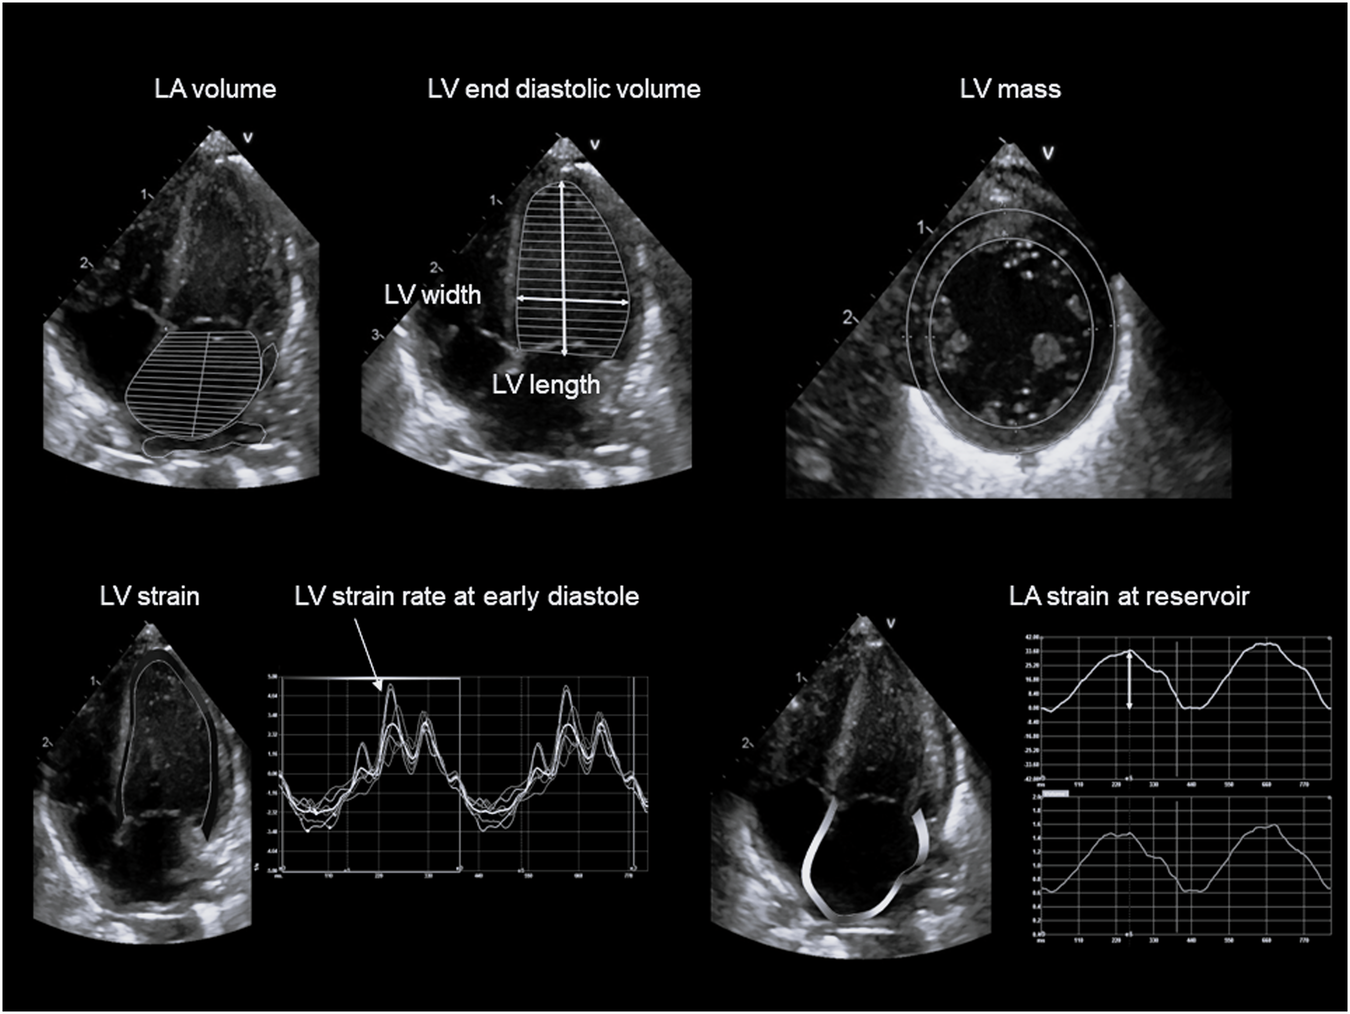

Fig. 2

Examples of ultrasound measures of left atrial and ventricular shape and size, mass, longitudinal strain and strain rate.